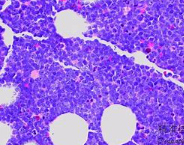

B淋巴细胞是一类由骨髓中的造血干细胞发育而来的淋巴细胞。它们主要存在于淋巴组织(如脾脏、淋巴结)和黏膜组织(如肠道和呼吸道)。B淋巴细胞具有特殊的受体,称为B细胞受体(BCR),它能够识别并结合病原体表面的抗原。

2、疾病诊断:在某些疾病,如自身免疫疾病、某些类型的白血病和淋巴瘤等,B淋巴细胞的数量和功能可能会发生改变。通过检测B细胞的数量和抗体水平,医生可以帮助诊断这些疾病。

5、参与疾病:B淋巴细胞在某些疾病中发挥着重要的作用。例如,在自身免疫疾病中,B细胞可能会产生自身抗体,攻击人体自身组织;在淋巴瘤等癌症中,B细胞可能会失控增殖,导致恶性肿瘤的形成。